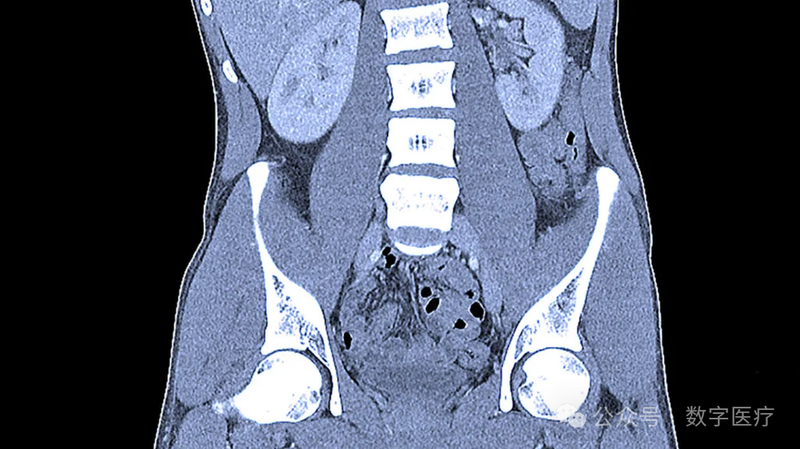

“莫林”是一个针对3D计算机断层扫描(CT)的视觉语言基础模型,该模型由美国斯坦福大学等机构的研究人员共同开发。

在医学影像领域,计算机断层扫描(CT)是一种关键的诊断工具,每年在美国进行超过8500万次CT扫描,其中约四分之一集中在腹部。随着医学影像利用的年增长率达到6%,放射科医生的负担日益加重,而放射科医生的数量却相对恒定。为了缓解这一压力,人工智能(AI)在医学影像解释中的应用变得尤为重要。传统的视觉语言模型通常局限于2D图像和简短报告,而且并未利用电子病历数据进行监督。相比之下,“莫林”能够处理3D CT图像的视觉语言模型,它结合了结构化的电子病历和非结构化的放射学报告,无需额外的人工标注即可进行监督学习,从而在医学图像解释方面展现出更广泛的应用潜力。

“莫林”模型通过“对比语言-图像预训练”技术,将文本和视觉表示在共享嵌入空间中对齐,从而实现对视觉模型的自然语言监督。这种范式使得利用互联网规模的图像和标题,展示出在即插即用(零样本)设置或随后适应(少样本学习)中的卓越图像理解能力。“莫林”使用高质量的临床数据集进行训练,该数据集包含配对的CT扫描(来自15331次CT扫描的600多万张图像)、电子病例中的诊断代码(180多万个代码)和放射学报告(600多万个标记)。

模型经过6种任务类型和752个单独任务的评估,展示了其在多种医疗影像任务中的优异性能。这些任务包括无需适应的(即现成的)任务,如零样本发现分类(31个发现)、表型分类(692个表型)和零样本跨模态检索(图像到发现和图像到印象),以及需要模型自适应的任务,如5年疾病预测(6种疾病)、放射学报告生成和3D语义分割(20个器官)。在内部测试集上,“莫林”在30个腹部CT发现上的零样本分类平均F1分数为0.741,在外部验证数据集上为0.647,显著优于其它两个相关模型。此外,“莫林”在预测692种表型方面的性能表现良好,其中37%的表型AUROC超过0.85,15%的表型AUROC超过0.9。